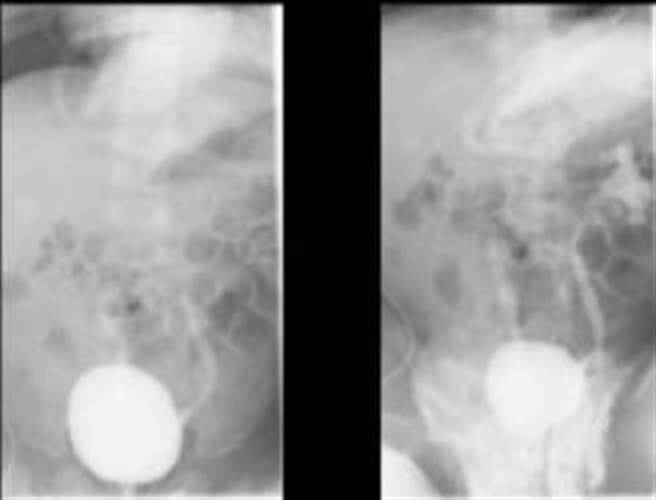

不过杨岱璟表示,泌尿道感染和多久换尿布并无很大关系,除了细菌有可能由尿道进入体内,还有便便里的细菌也可能经由泌尿道而引发感染。另外,有些新生儿泌尿道系统若有缺陷,而有尿液从膀胱逆流到输尿管的情形,也可能造成泌尿道感染。而女生天生尿道较短,泌尿道感染机率也较高,因此女婴反覆感染2次以上,就应该做输尿管逆流摄影检查以确认有无异常。

杨岱璟说明,新生儿泌尿道感染若未及时治疗,细菌在反覆发烧下,也可能进入血液,引发败血症甚至休克。严重婴幼儿泌尿道感染也必须使用抗生素治疗至少5到7天,同时安排肾臟超音波检查是否有肾盂扩大现象,必要时安排输尿管逆流摄影以了解泌尿道发育状况。